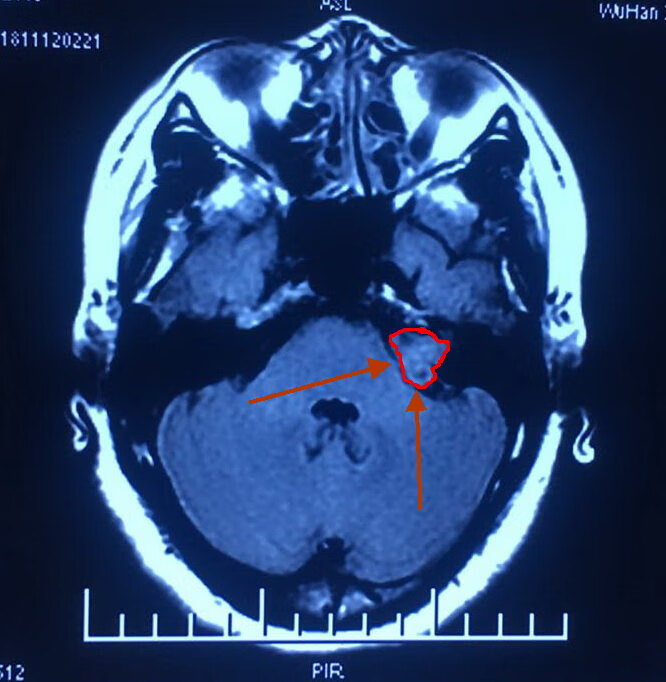

她,45岁,左耳失聪三年。经过核磁共振检查发现左侧桥脑小脑角区占位性病变,考虑听神经瘤。

肿瘤大小1.8cm。

术前影像如下:

术前内听道CT显示左侧内听道口较对侧明显扩大,呈喇叭口状。